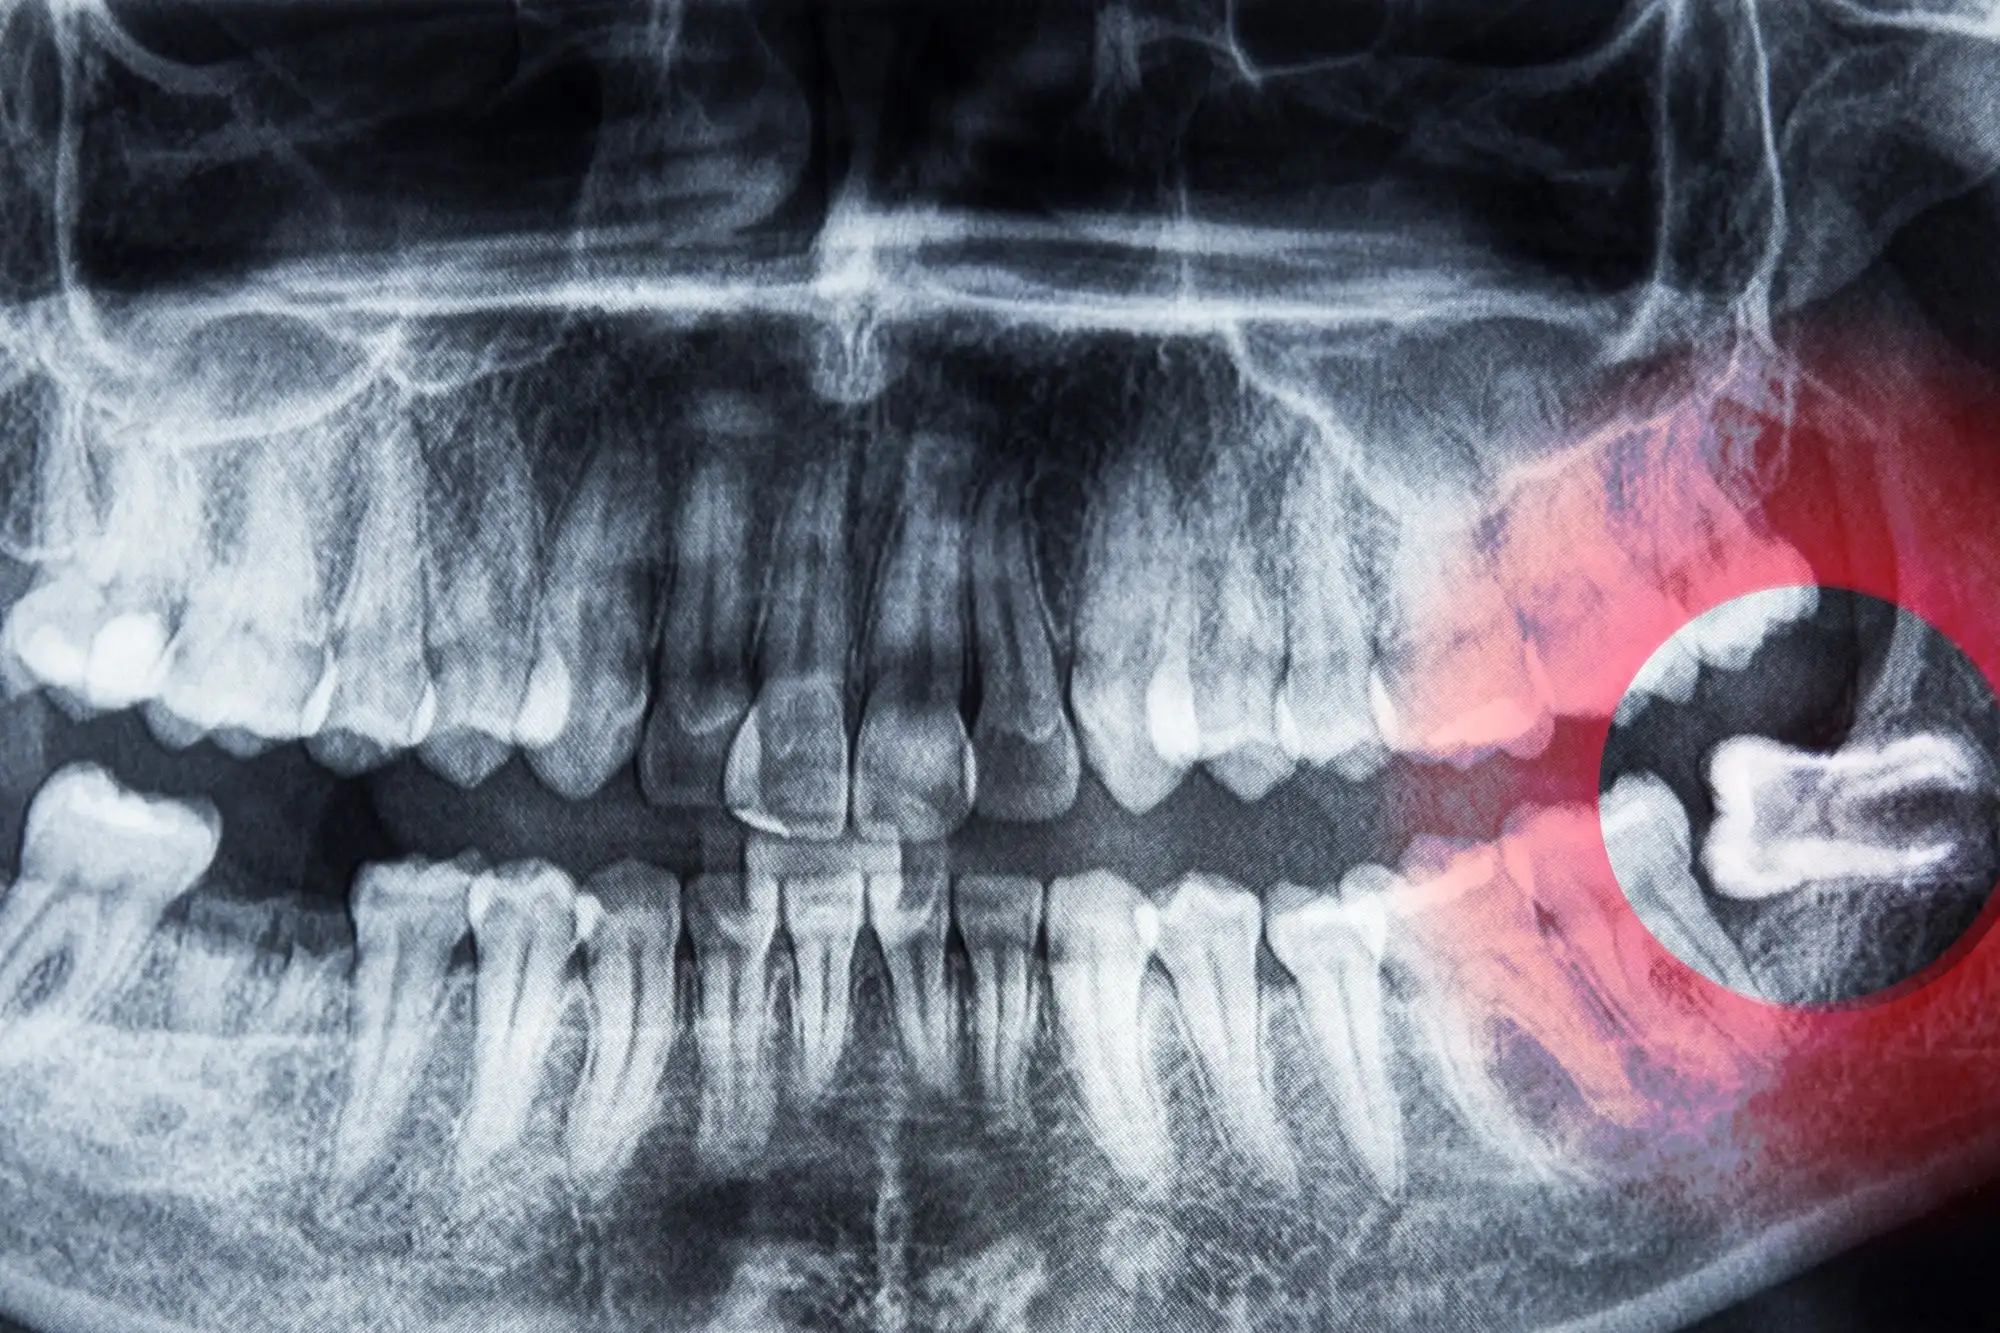

Your orthodontist will evaluate your wisdom teeth development through dental X-rays to determine if they pose any risk to your treatment outcomes.

The key is proper assessment. Your orthodontist will use panoramic X-rays and possibly 3D imaging to evaluate how your wisdom teeth might interact with your planned orthodontic treatment.

Dental Imaging and How It Guides Treatment Decisions

Modern dental imaging plays a crucial role in wisdom teeth evaluation:

Panoramic X-rays provide a comprehensive view of all teeth, including developing wisdom teeth, showing their position and angle of eruption.

Cone Beam CT scans (CBCT) offer detailed 3D images that reveal:

– Exact tooth positions and impaction types

– Proximity to nerves and sinuses

– Root structure and development

– Available jaw space

– Potential complications

Digital models help simulate treatment outcomes with and without wisdom teeth present.

These imaging tools allow your orthodontist to make evidence-based recommendations rather than guesswork. They can show you exactly what’s happening beneath your gums and explain how wisdom teeth might affect your treatment.